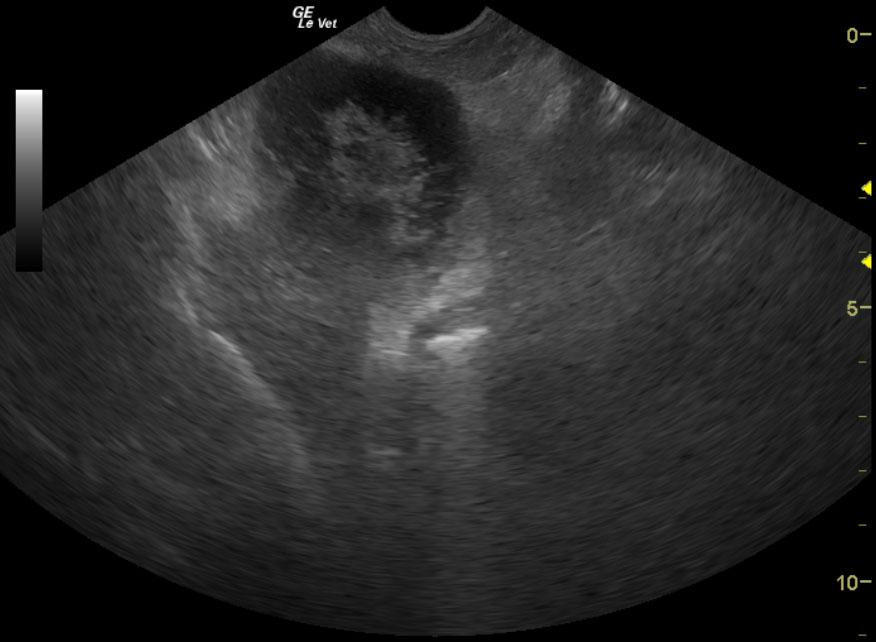

A 12-year-old NM Maltese with a history of pituitary dependent hyperadrenocorticism that was being treated with Lysodren was presented for vomiting, anorexia and not doing well over a 2-day period. Urinalysis showed an inappropriate SG (1.018), proteinuria, and bilirubinuria. Abnormalities on CBC and serum biochemistry were leukocytosis, severely elevated ALT and severely elevated ALP activity, hypoalbuminemia, bilirubinemia, and azotemia. The patient was treated with antibiotics, to which there was some response.